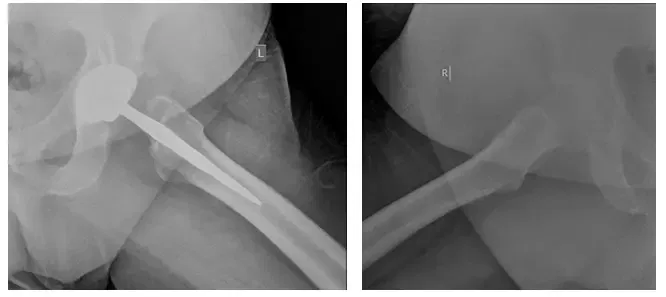

Radiographie de la hanche gauche pendant le fonctionnement

Radiographies de la hanche gauche pendant le fonctionnement

Les radiographies montrent des changements peropératoires, y compris la mise en place de THA à longue tige, 2 vis fixant l’acétabulum et des fils de cerclage entourant le fémur. Les radiographies montrent également un ostéolisme trochantérien étendu de la tige fémorale proximale d’un tiers qui est fixée avec des fils de cerclage.